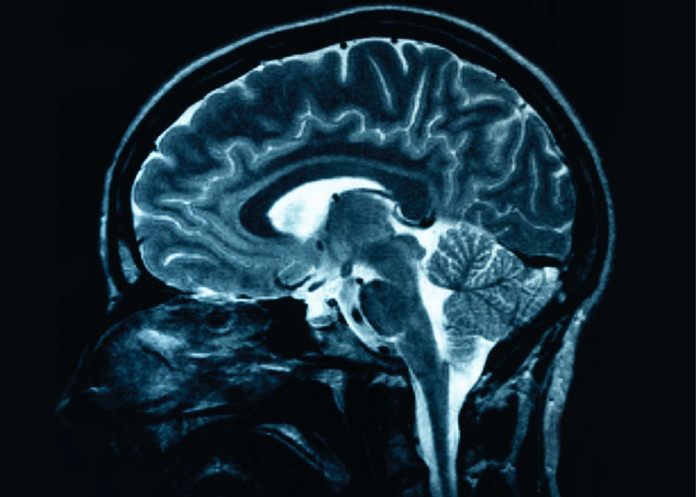

«Nuestros resultados del estudio demuestran por primera vez que la señalización de la insulina en el cerebro de los mamíferos regula los niveles de BCAA aumentando desglose BCAA en el hígado», dice el Dr. Christoph Buettner, profesor asociado de medicina en la Escuela de Medicina de Icahn y autor principal del nuevo estudio.

«Esto sugiere que los BCAA en plasma elevados son un reflejo de la alteración de señalización cerebral de la insulina en individuos obesos y diabéticos,» él dice.

«Lo importante es que los roedores con una alteración de la insulina de señalización exclusivamente en el cerebro tienen niveles elevados de BCAA en plasma y deficientes desglose BCAA en el hígado.

Dado que la señalización de insulina cerebro perturbado puede causar que el aumento temprano de BCAA observarse en personas que finalmente desarrollan diabetes, la resistencia a la insulina que conduce a la diabetes puede comenzar realmente en el cerebro. Los resultados sugieren que los niveles de BCAA pueden resultar para reflejar cerebro sensibilidad a la insulina «.